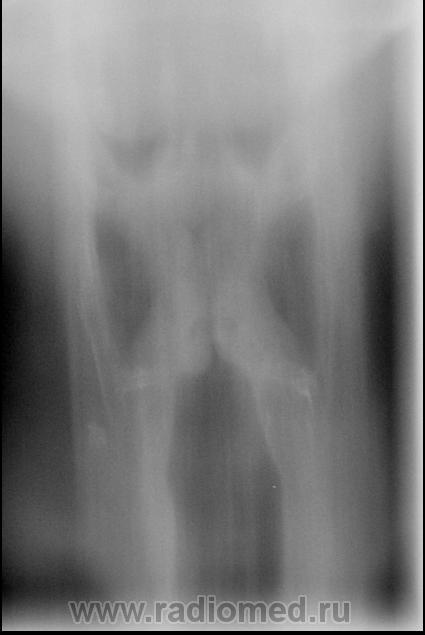

Мужчина 65 лет. Жалобы на осиплость голоса в течение 3 недель. Стаж курения 50 лет.

По тому, что есть, я не могу уверенно сказать об опухоли. В принципе, всё симметрично. Сам делаю 4 снимка: а)фонация "у" громко, чтоб в пультовой было слышно; б) в покое; в) на медленном продолжительном вдохе и г) в напряжении (попытка выдоха через сомкнутую голосовую щель). Предпочитаю делать снимки сам, со скопии. Но навязывать такую медоту очаровательной девушке не смею!

Присоединяюсь к коллеге.Симметрия не нарушена.